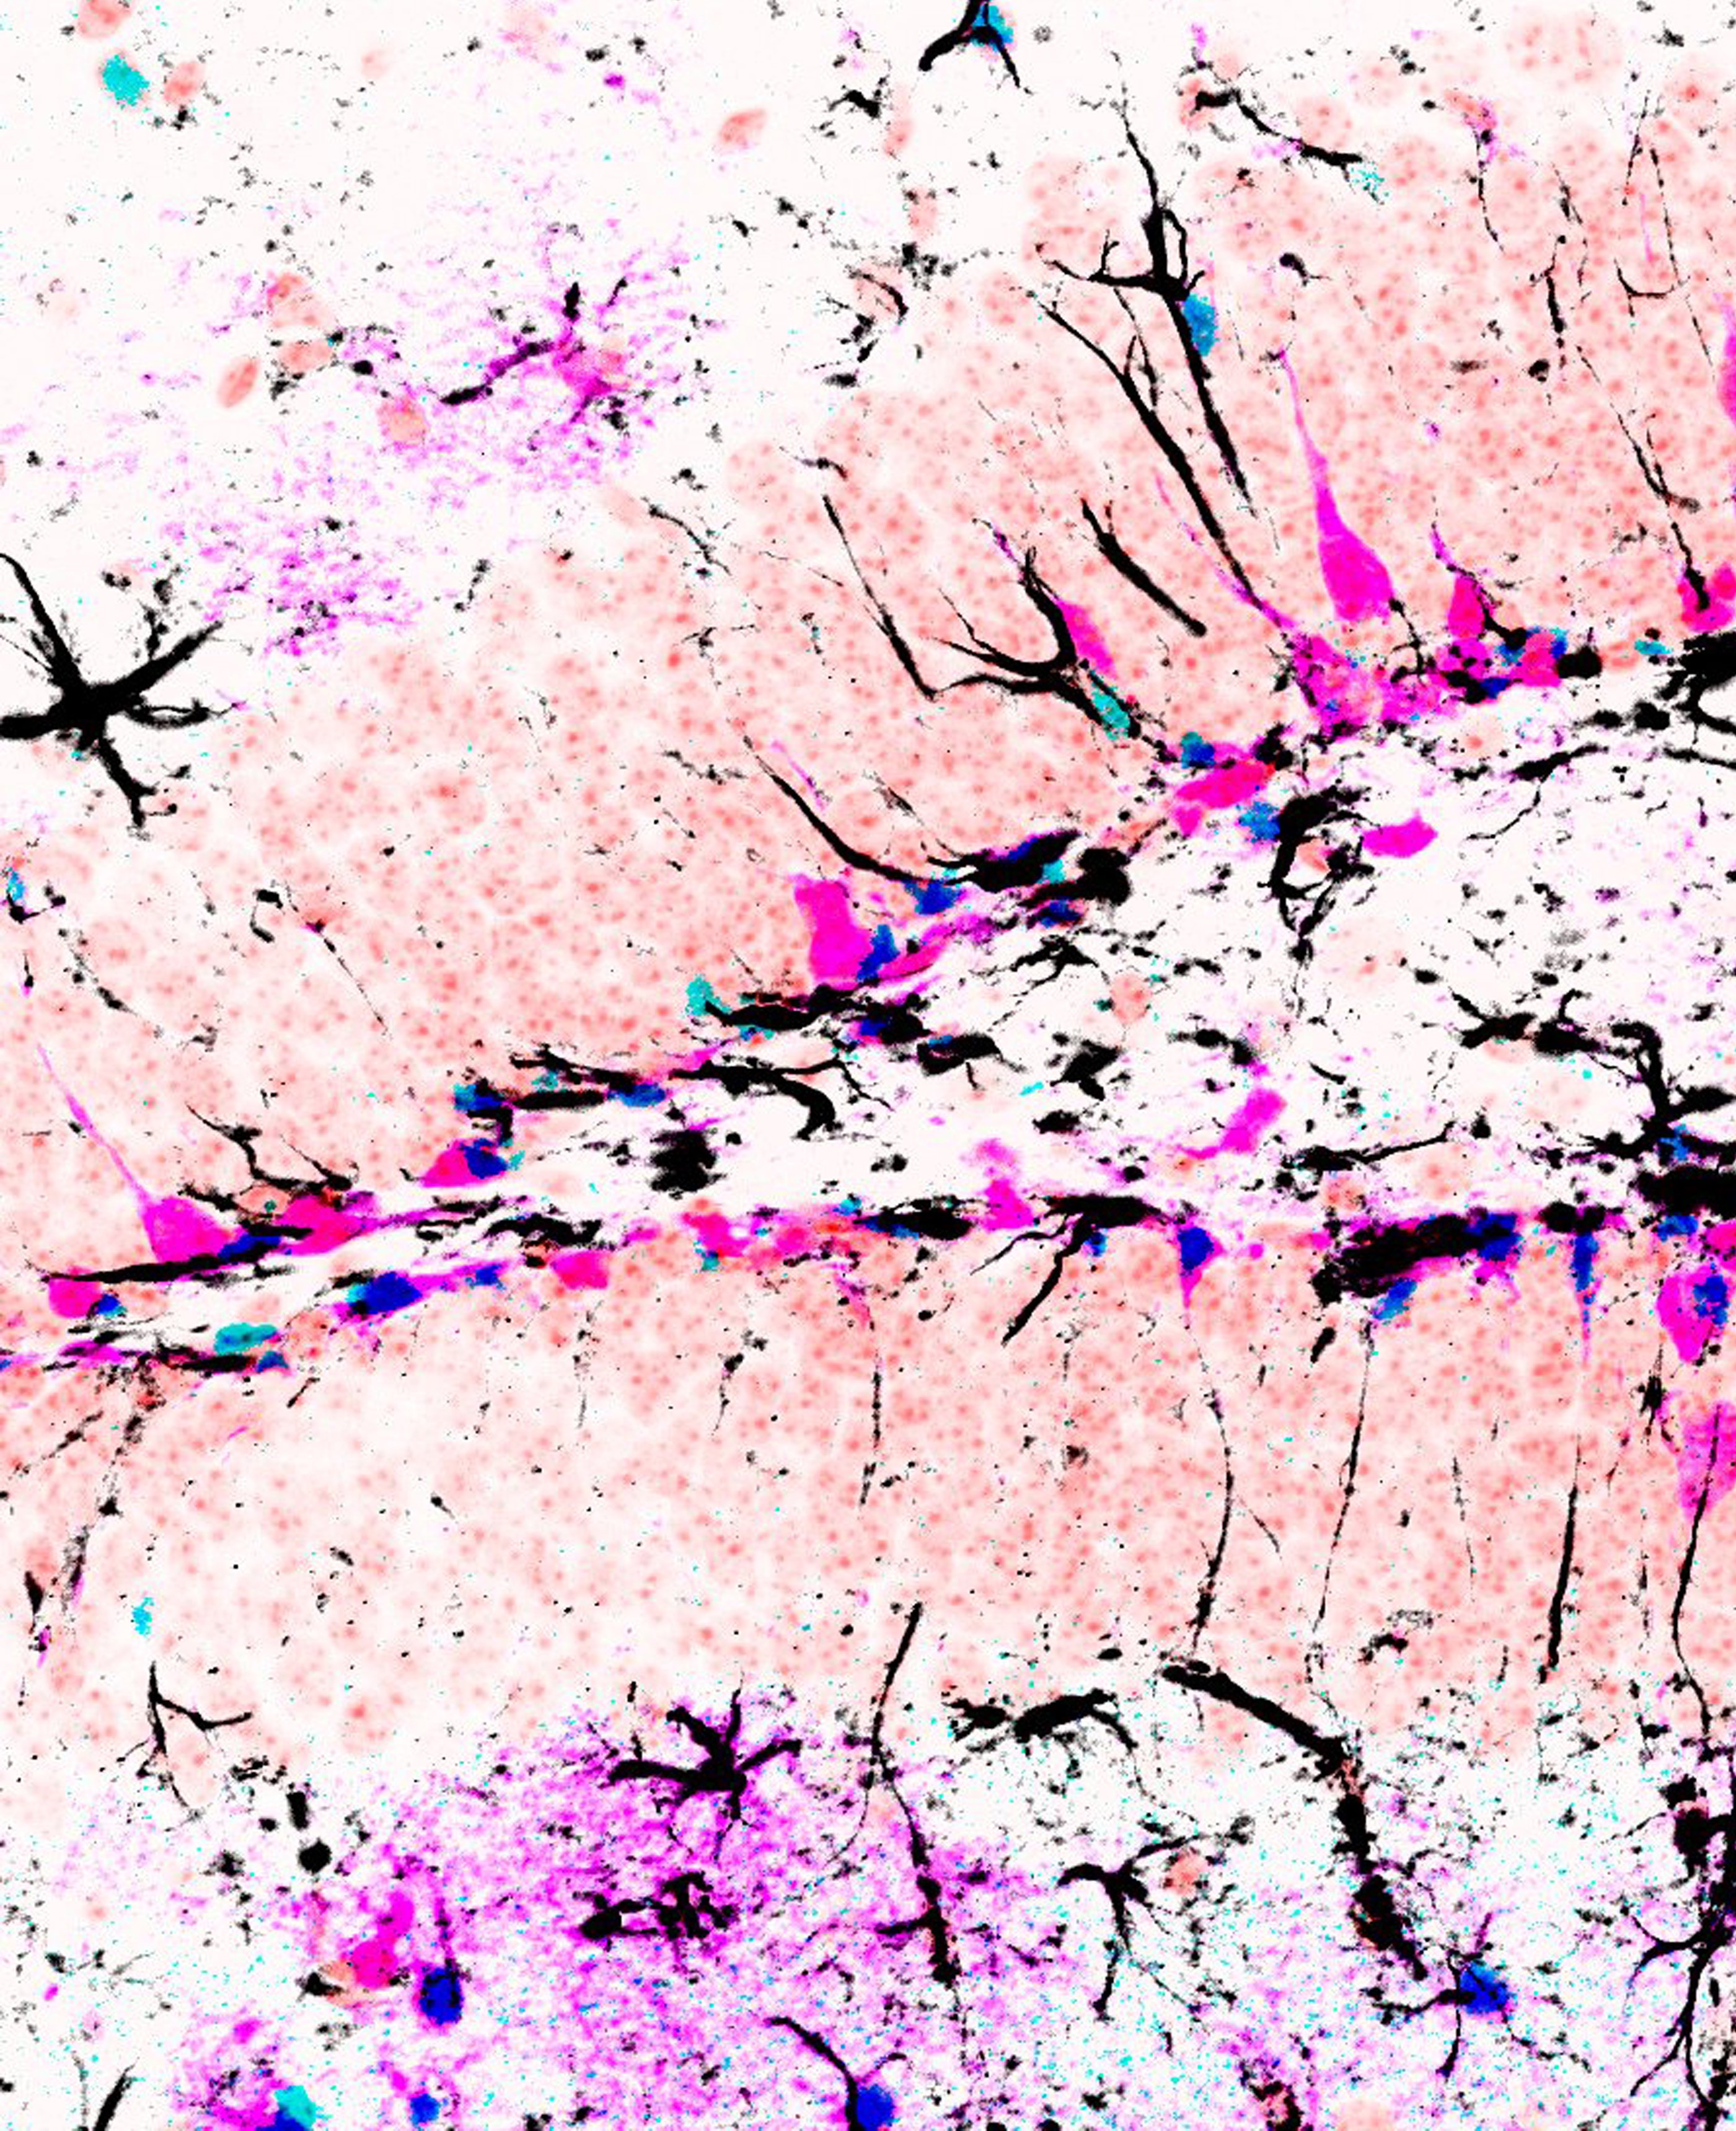

Die Studie zeigt, dass der Notch2-Signalweg die Expression eines bestimmten Transkriptionsfaktors namens Id4 kontrolliert. Einmal exprimiert, hemmt Id4 die Teilung von Stammzellen wie auch die Produktion neuer Neuronen im Hippocampus des erwachsenen Gehirns. Das Notch2-Signal induziert eine erhöhte Id4-Expression in einigen neuronalen Stammzellen. Das erklärt, warum diese Stammzellen im erwachsenen Gehirn vermehrt in eine Art Ruhezustand übergehen.

Mit zunehmendem Alter des Gehirns tritt der Notch2-Id4-Signalweg in einen dauerhaften Zustand der Hyperaktivität und fungiert so als starke molekulare Bremse für die Stammzellenaktivität. Umgekehrt gilt aber auch: Wird der Signalweg inaktiviert, löst das die Bremswirkung und führt in Folge zur Produktion von neuen Nervenzellen – selbst im Gehirn einer geriatrischen Maus.

Die Ergebnisse zeigen, dass sich die Stammzellen im Gehirn von Säugetieren in einem reversiblen Ruhezustand befinden, der durch Signale und Faktoren in der Nische reguliert wird. Durch eine entsprechende Manipulation des Signalwegs kann die Produktion neuer Nervenzellen gezielt stimuliert werden.